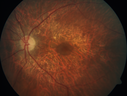

Concentric Geographic Atrophy - 76 year old man359 viewsGradual vision loss, worse at night. VA 20/40 OU.     (0 votes)

76 year old man The patient has noticed that his vision is getting worse at night. The vision loss has come on gradually. He notices that his vision in low lighting is poor and at night with oncoming headlights.

VA OD: Dcc20/40-1 NscJ7

VA OS: Dcc20/40-1 NscJ7

IOP: TP: OD:17 OS:18 Time:12:01 PM